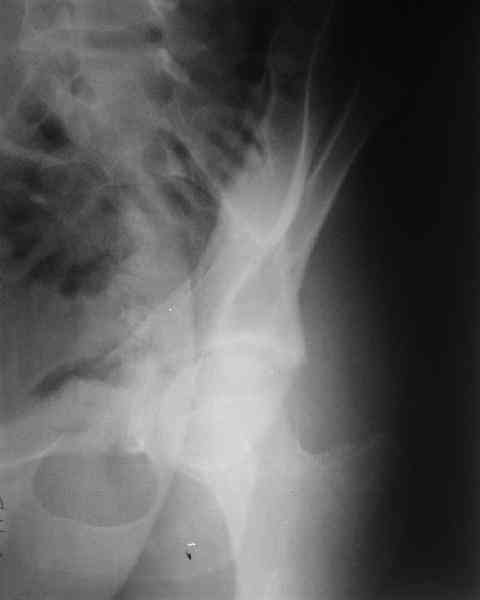

Нелеченный перелом вертлужной впадины

Мужчина 33 лет получил травму в шахте (придавило вагонеткой) 6 недель назад. Изолированное повреждение вертлужной впадины.

В местной больнице отлежал несколько недель на вытяжении. После выписки амбулатрный травматолог направил в институт. На сегодня, похоже, уже имеется неправиильное сращение. См. картинки.

Вопрос - что делать сейчас? Оставить как есть или идти на открытое восстановление? Если последнее, то какой доступ, репозиционные манипуляции и фиксацию тут можно посоветовать? Заранее спасибо.

Dear all, A male 23 y.o. injured 6 weeks ago - mine trauma, impacted by a carriage. Isolated injury of the acetabulum. At the initial hosptial was on bed traction some weeks. After discharge visited anotheк orthopaedic surgeon who referred him to our unit. To date looks like a malunion. Images attached. The question is about what to do now - either leave it as is or perform open reduction? If the latter what approach, reduction manoeuvres and fixation would you advice? Thx in advance!